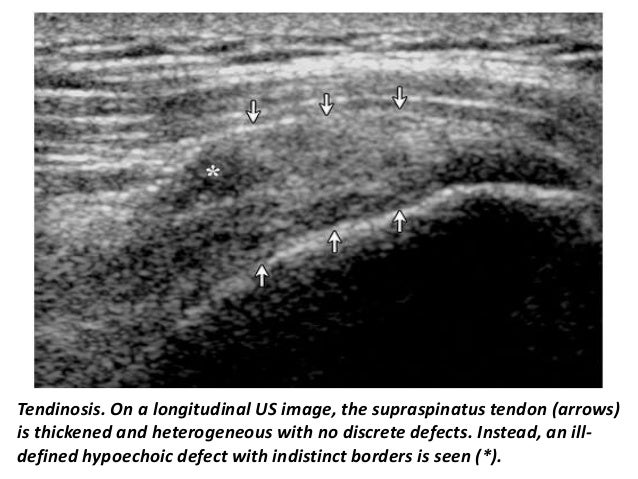

34. 34. Tendinosis. On a longitudinal US image, the supraspinatus tendon (arrows) is thickened and heterogeneous with no discrete defects. Instead, an ill- defined hypoechoic defect with indistinct borders is seen (*).